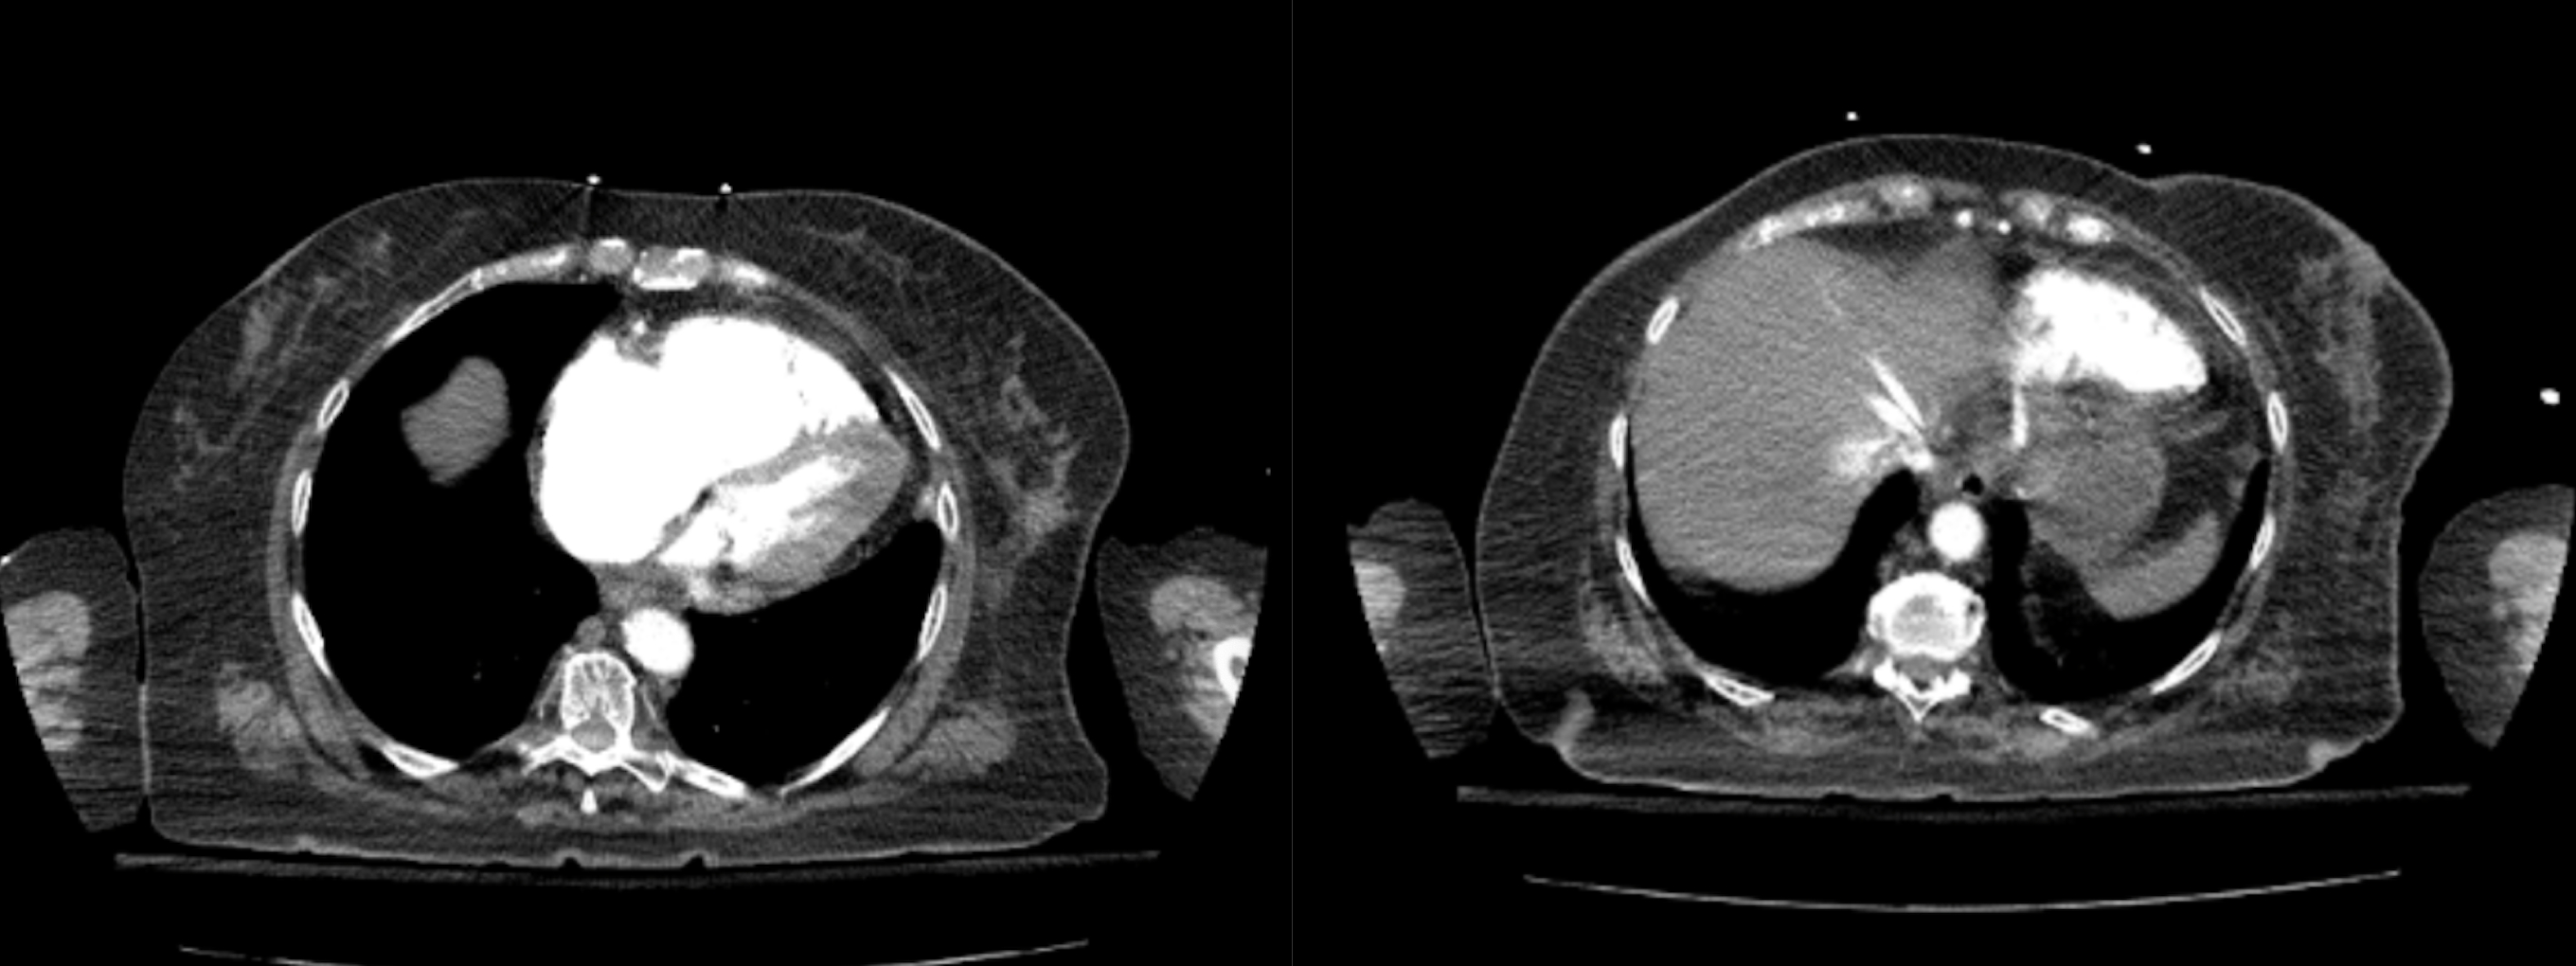

An ECG demonstrated sinus tachycardia with S1Q3T3 pattern, incomplete right bundle branch block (RBBB), inverted T wave in V1 and V3. Her Daniel Score was calculated at 9, indicating a high risk for hemodynamic instability. Troponin was 0.10 and BNP 8030. PE was suspected and a CTA confirmed a large saddle PE involving both main pulmonary arteries, with signs of RV strain, including RV dilation and contrast reflux into the IVC.